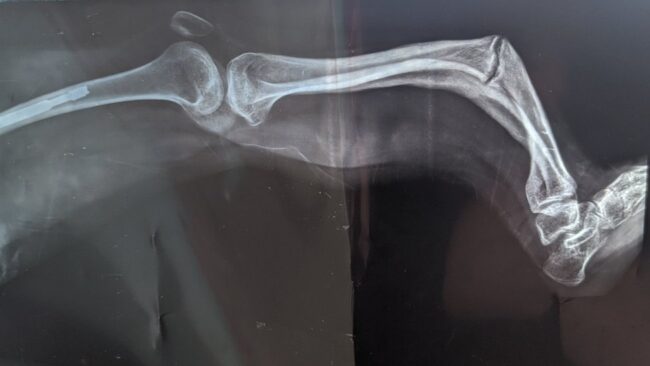

Jovem conta como é viver com doença dos ossos de vidro: ‘Já sofri 100 fraturas’

Desde bebê, a estudante paulista Beatriz Fernandes da Silva, hoje com 20 anos, precisa tomar cuidado para não cair e se machucar.Quando ainda estava na barriga da mãe, os médicos perceberam algo diferente durante o ultrassom e alertaram que a criança poderia nascer com algum tipo de osteopenia ou até nanismo.Doença de Wilson: ‘A enfermidade…